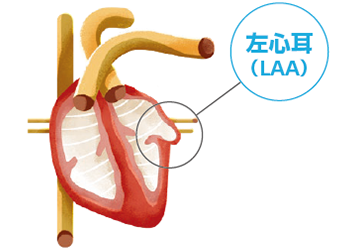

非弁膜症性心房細動の患者さんでは、脳卒中の原因となる血栓の90%以上が左心房に起始する左心耳(LAA:Left Atrial Appendage)で形成されたものです。

WATCHMANはこのLAAを閉鎖して血栓の形成を防ぎます。手技は経静脈的心房中隔穿刺法であり、カテーテル室において全身麻酔下で実施します。

左房に存在する左心耳(LAA)というポケットに血栓が形成され、これが脳やほかの臓器に流れて梗塞(塞栓)を引き起こします。

WATCHMANは心臓の左心耳(LAA)と呼ばれる部分に留置されます。

WATCHMANは時間が経つと、内皮に覆われて完全にLAAを閉鎖します。

心房細動は、心臓の上部にある2つの部屋(心房)が小刻みで不規則な拍動(細動)をする不整脈です。この疾患によって、心臓の左心耳(LAA:Left Atrial Appendage)に血液が滞留して血栓が形成されることがあります。血栓が動脈を通って脳に達すると脳卒中に至る場合があります。

- 非弁膜症性心房細動では、左心耳(LAA)と呼ばれる小さな袋で形成される血栓が脳卒中の主な原因と考えられています。